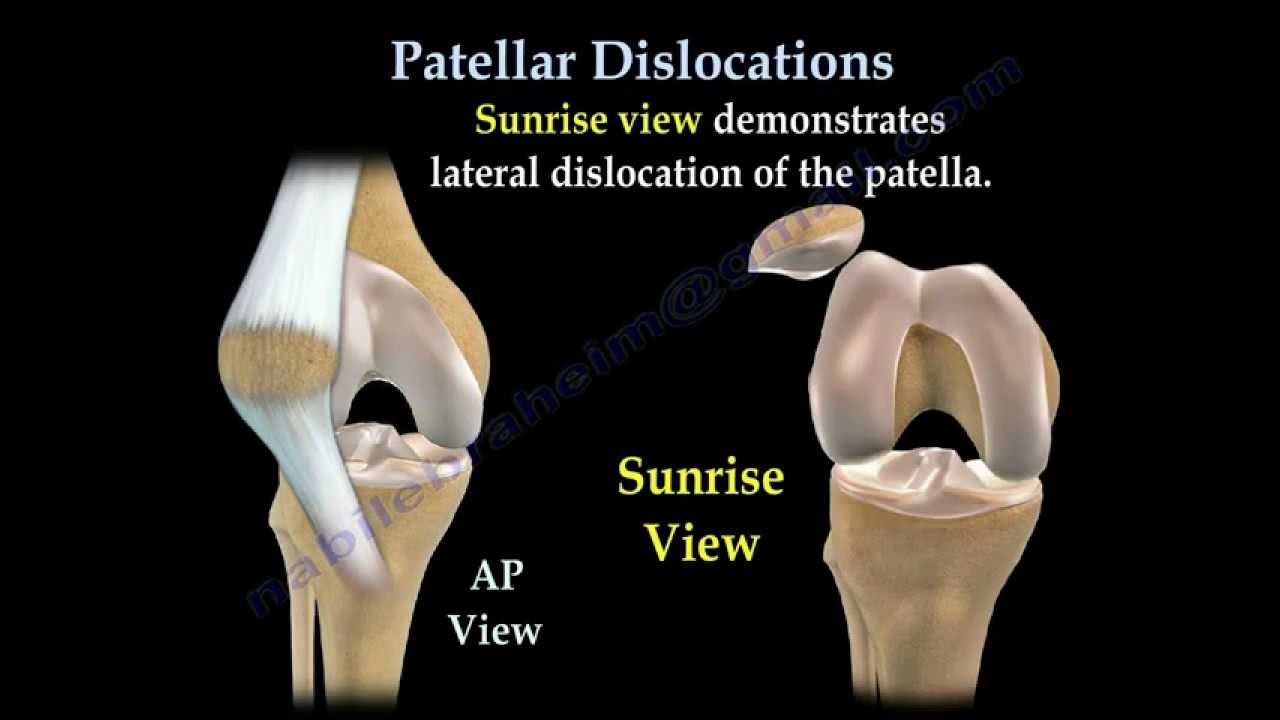

Knee dislocation Wikipedia sale, Knee Dislocation Trauma Orthobullets sale, Knee Dislocation Practice Essentials Prognosis sale, Knee dislocation Wikipedia sale, Luxating patella in dogs PDSA sale, Anterior knee dislocation Radiology at St. Vincent s University sale, Knee Dislocation Trauma Orthobullets sale, Luxating Patella in Dogs Knee Dislocation Symptoms Causes sale, Knee joint dislocations illustrations Radiology Case sale, Dislocated Knee Hartford Hospital Hartford CT sale, Knee Dislocation Practice Essentials Prognosis sale, Knee Dislocation Orthopaedic Trauma Association OTA sale, Knee Dislocation Multi ligament Knee Injuries Lamberti sale, Patellar dislocation Physiopedia sale, Kneecap Dislocation sale, All About Knee Dislocations USF Emergency Medicine sale, Patellar Subluxation Subluxed Partially Dislocated Kneecap Facts sale, Knee dislocation Radiology Reference Article Radiopaedia sale, Posterior knee dislocation Radiology at St. Vincent s University sale, Two years neglected knee dislocation An unusual case report sale, Knee Dislocation Orthopaedic Trauma Association OTA sale, Dislocated Knee Knee Surgeon Minnesota sale, Knee Dislocation Orthobridge Orthopaedic Institute sale, True Knee Patellar Dislocations Core EM sale, Kneecap Dislocation Patellar Subluxation Treatment Symptom Causes sale, Patellar dislocation LITFL Trauma Library sale, Knee dislocation Radiology Case Radiopaedia sale, Patella luxation in dogs Joii Pet Care sale, Medial Patella Luxation Queensland Veterinary Specialists sale, Patella Luxation Warren House Veterinary Centre sale, Patellar luxation Marshalswick Veterinary Surgery sale, Patella Luxation Smart Approach Veterinary Services sale, Patellar luxation Fitzpatrick Referrals sale, Patellar Dislocations Everything You Need To Know Dr. Nabil Ebraheim sale, Medial Luxating Patella Grades of Dislocations Surgery and sale.